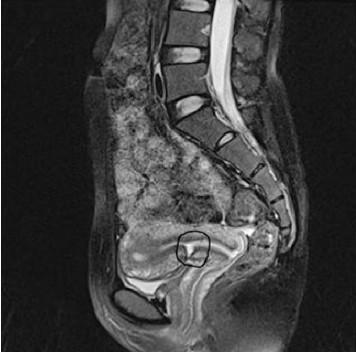

4.磁共振 可见憩室部位子宫内膜及肌层不连续,肌层部分或全部缺损,但不作为常规检查。

PCSD的MRI影像(黑色线圈处所指即是)